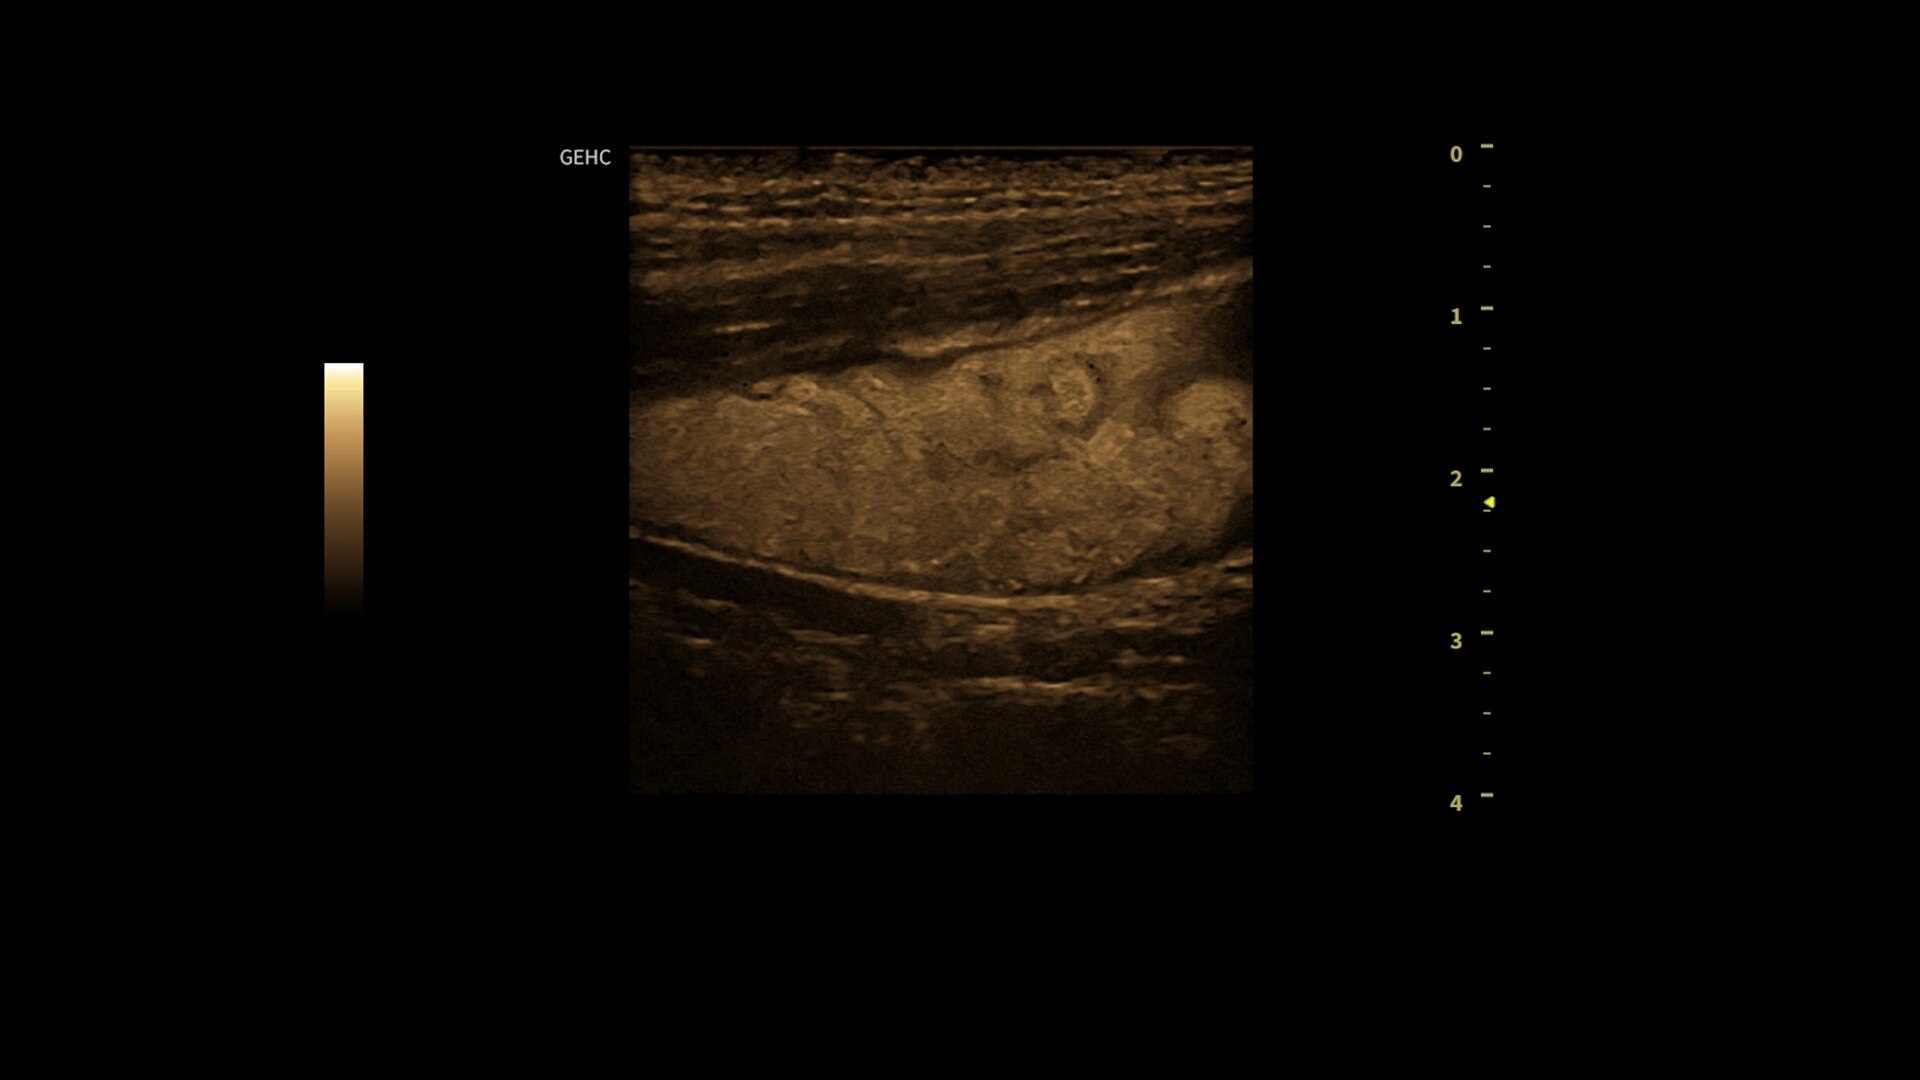

Powered by VisionBoost Architecture, Versana Premier provides optimal image quality so users can easily reach a diagnosis. Advanced clinical features help address challenging cases while automated tools help reduce scan time:

• Optimize images while scanning with Whizz clinical features, easily improve Color Doppler with Whizz Color Flow, and view scans in the image style that suits your preference with Whizz Easy Style

• Use automated labeling in the RUQ with Whizz Label

• Make automated 2D Measurements and Volume Calculations with Auto Contour, Auto Bladder, Whizz Follicle and Auto-IMT

• Assess liver, thyroid and breast nodules with Productivity Packages leveraging LI-RADS,® TI-RADS® and BI-RADS® criteria*